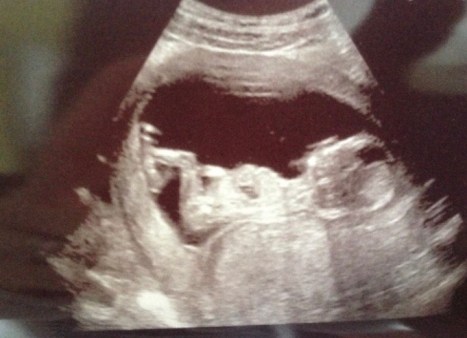

We were so thrilled to be expecting our first child and already had big plans for how we would decorate the nursery and all the things we should buy for the baby when we went for our 20 week scan not long before Christmas in 2014. It was then that everything changed, the horrible moment when the sonographers turned their back and clearly discussed that something was not right… we were referred to the specialist team at the RVI in Newcastle for further scans and this is where we found out that Evie had problems with her heart, a combination which they had never seen before. Our world fell apart, yet we decided that what we had to do was be positive and do everything we could for her.